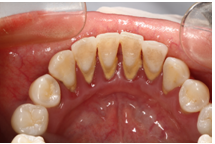

1、牙周病

牙周病是导致拔牙的主要原因之一。牙周炎会导致牙齿周围的骨头吸收,进而导致牙缝变大、前牙黑三角出现,牙齿松动、咀嚼无力等情况。治疗牙周病基本的方法就是定期牙周基础治疗,一般半年到1年,控制牙周炎的进展。